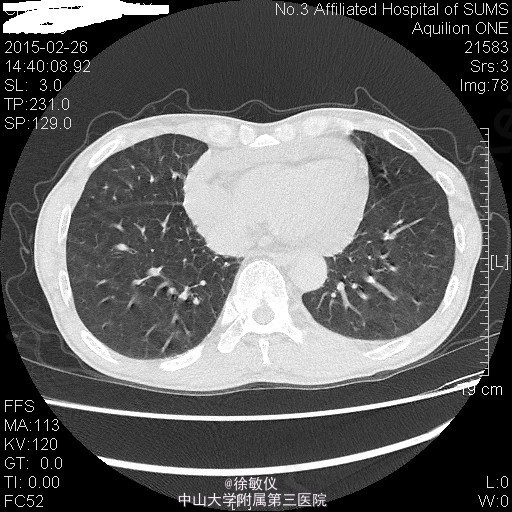

老年男性,主诉:咳嗽、咳痰2月余,头痛、纳差伴四肢乏力5天。 现病史患者2月余前无明显诱因出现咳嗽、咳痰,呈连声咳,咳白色稀薄痰,未予特殊治疗。5天前无明显诱因出现头痛,为右侧颞部持续性隐痛,尚可入睡,伴有纳差,四肢乏力。遂来我院门诊,查胸部CT示:1、左肺上叶尖后段空洞性病变;纵隔多发肿大淋巴结;中~大量心包积液。2、右肺中叶及双肺下叶少许慢性炎症。遂收入院。 查体:生命体征平稳,查体无特殊。 入院后予行心包穿刺抽液,心包积液检查:浆膜腔液总蛋白47.7g/L,乳酸脱氢酶306U/L,浆膜腔积液葡萄糖5.76mmol/L,白细胞计数2150X10E6,颜色黄色,粘蛋白定性试验+/-,红细胞计数1570X10E6,透明度微混,凝固物有凝块,淋巴细胞0.88,中性粒细胞0.12。血清 癌胚抗原>100ug/L。 血清乳酸脱氢酶:358U/L。 暂予头孢美唑钠(悉畅)注射剂2g Q12h,左氧氟沙星氯化钠(可乐必妥)注射液0.6g Qd抗感染治疗。 因患者诉头痛明显,行头颅MR提示:1右侧蝶骨嵴肿物,考虑脑膜瘤;双侧小脑半球及小脑蚓部肿物并双侧小脑半球脑沟脑回样强化,考虑转移瘤并脑膜转移,梗阻性脑积水。 诊断:1、心包积液 恶性肿瘤转移 2、高血压病 2级 高危 3、头部恶性肿瘤 颅内转移 4、脑膜瘤 5、肺部感染 患者肿瘤情况不明,出院后第二天因脑疝死亡。